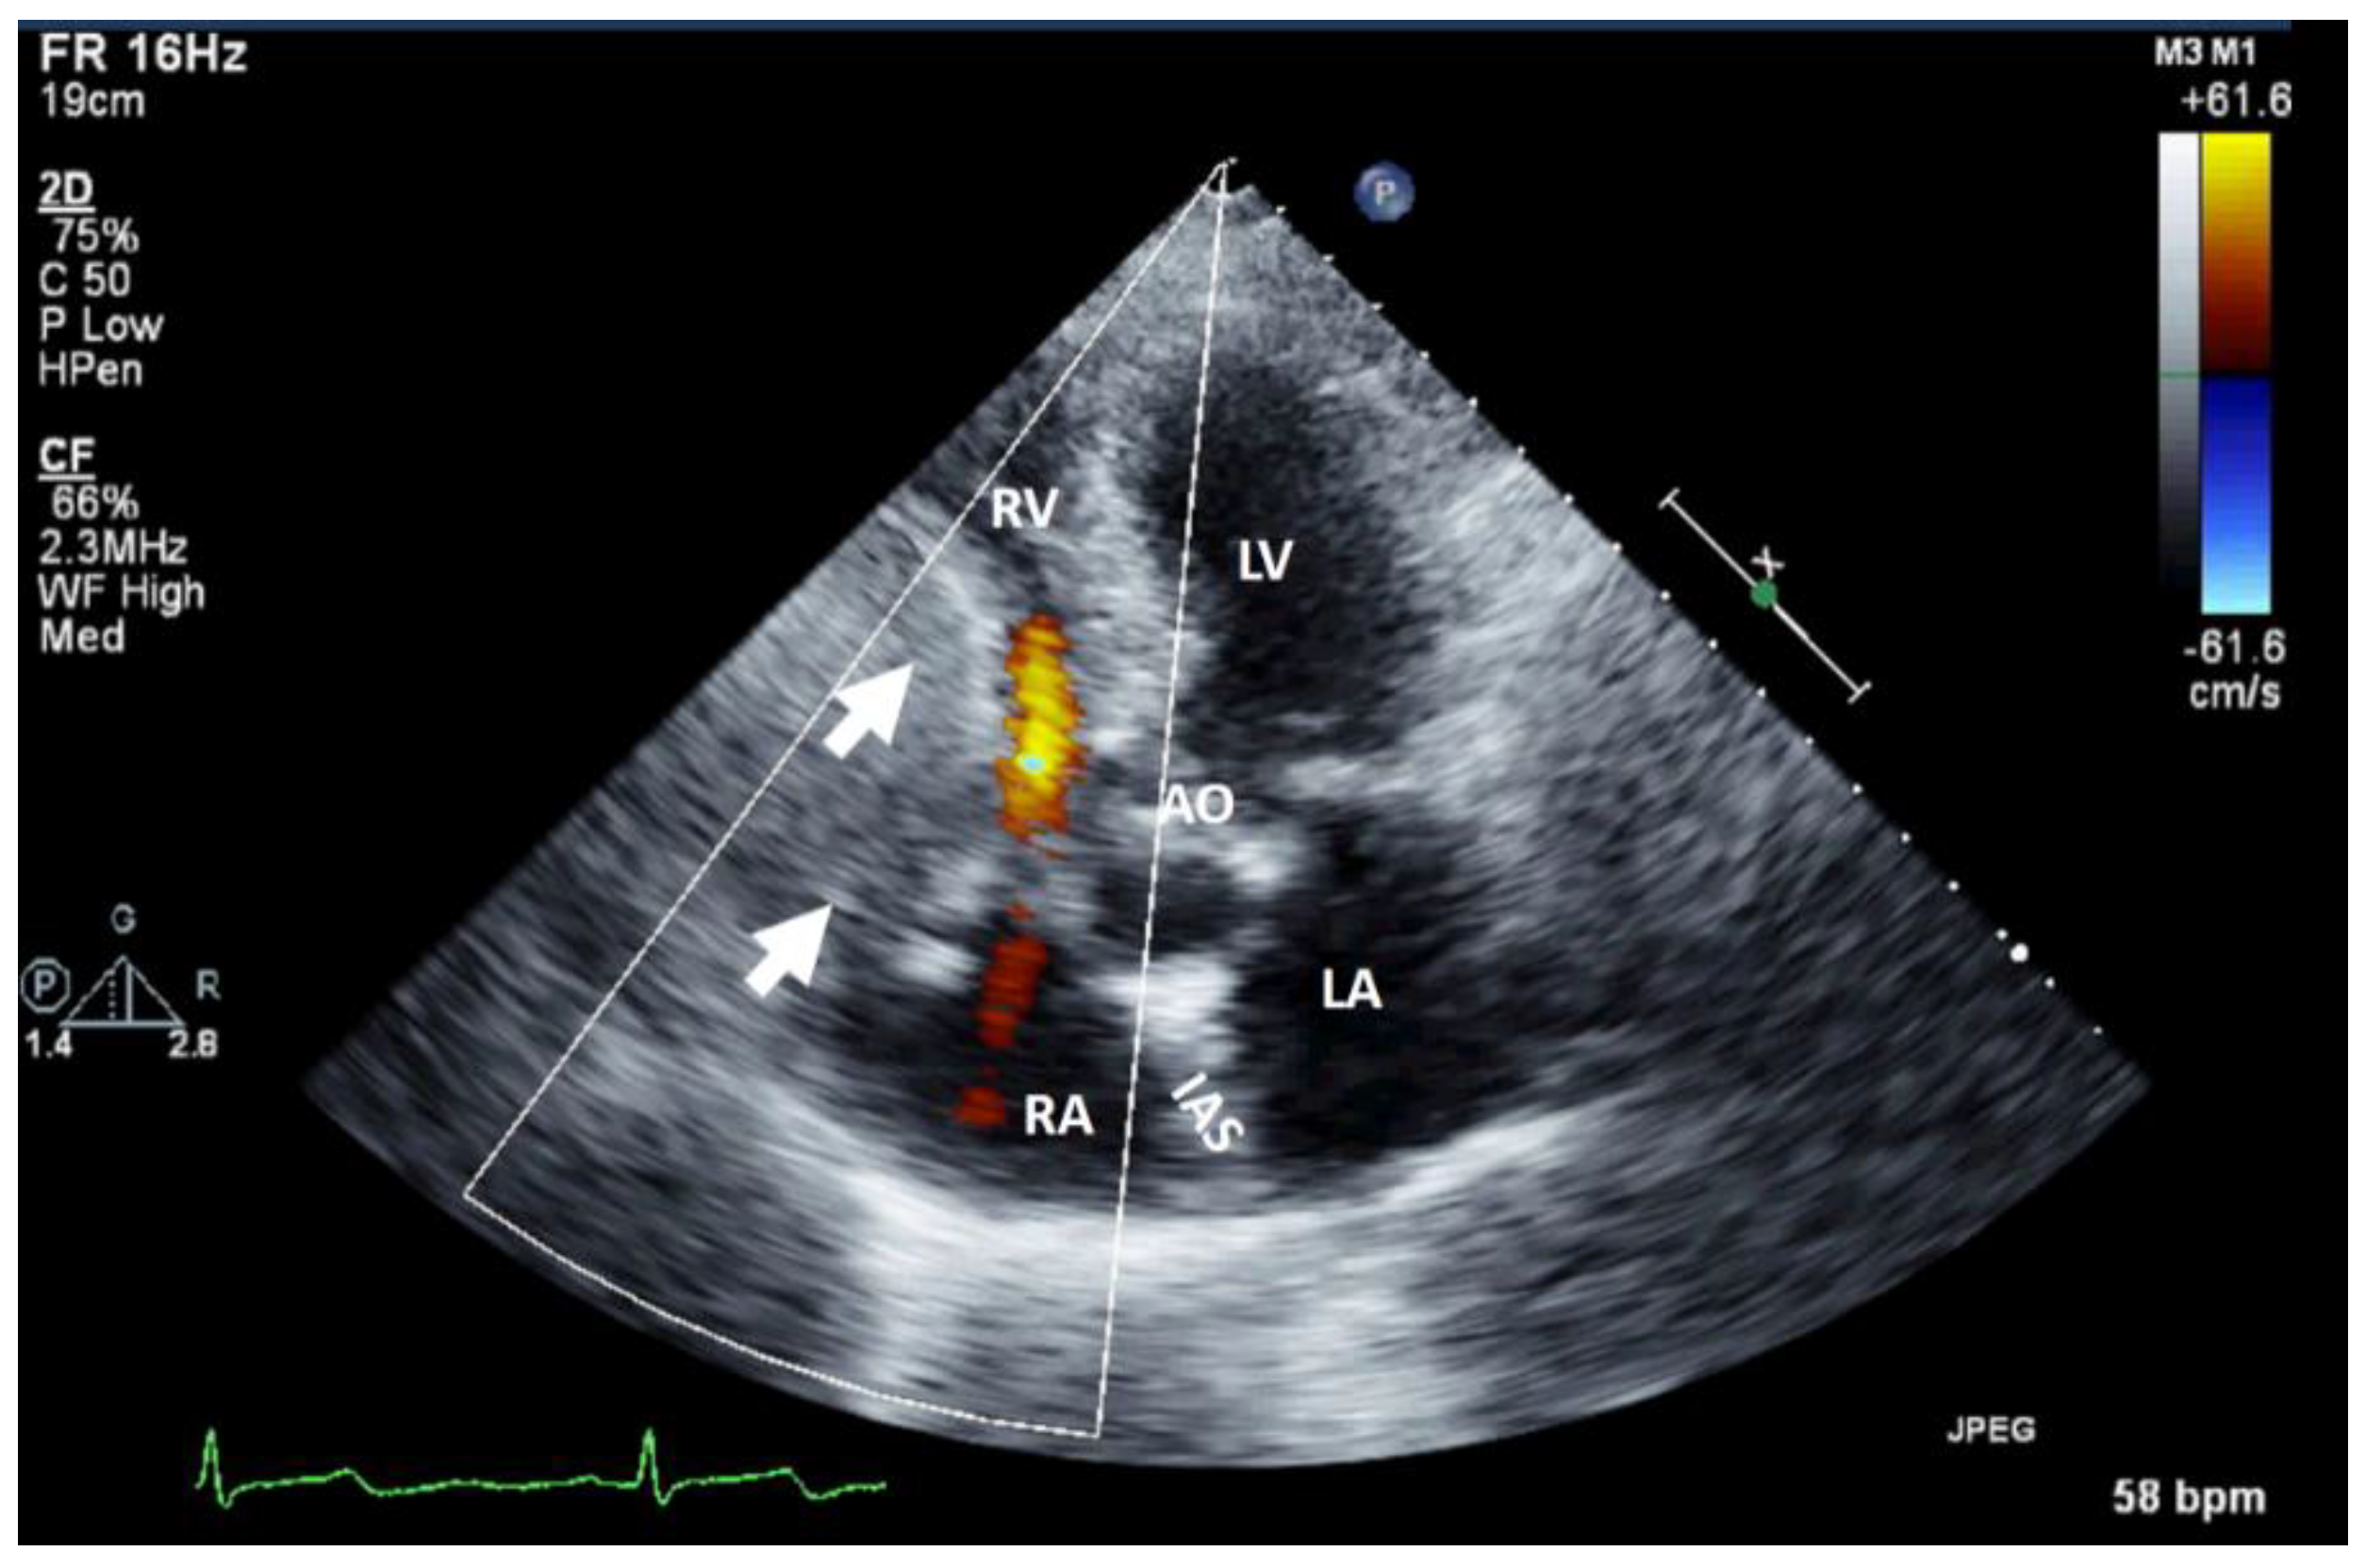

Figure 1. Bi-dimensional transthoracic echocardiography (apical 4 chambers view) with color Doppler showing external compression of the free right ventricular wall (arrow) in a patient with hepatomegaly due to a hepatic tumor, which explained hemodynamic instability (similar to a localized cardiac tamponade). AO, aorta; IAS, interatrial septum; LA, left atrium; LV, left ventricle; RA, right atrium; RV, right ventricle.

It can be used as screening imaging method, but right heart tumors could be an incidental finding during routine echocardiographic examination. This imaging technique is widely available (accessible), portable, easy to perform, even at the patient’s bedside and in those who are hemodynamically unstable. It is safe, repeatable without any consequence, cost effective, has a good spatial resolution (higher with TEE) and an excellent temporal resolution. TEE is more sensitive in identifying tumors less than <5 mm compared with TTE. Therefore, comparing with TTE, TEE is better for detection, location and mobility of cardiac tumors and equal for hemodynamic impact, compromising as compression/destruction/distortion of cardiac structures [12]. In some cases, the mass effect of a non-cardiac tumor severely compromises cardiac hemodynamics (Figure 1).